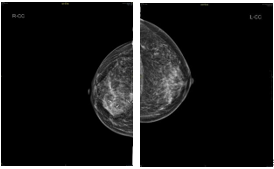

•  2018-10-16 钼靶:右乳内份肿块,BI-RADS 0

4疗程治疗后评估:CR

4疗程后MRI:右乳癌治疗后较前好转,BI-RADS:6。 右腋下小淋巴结同前